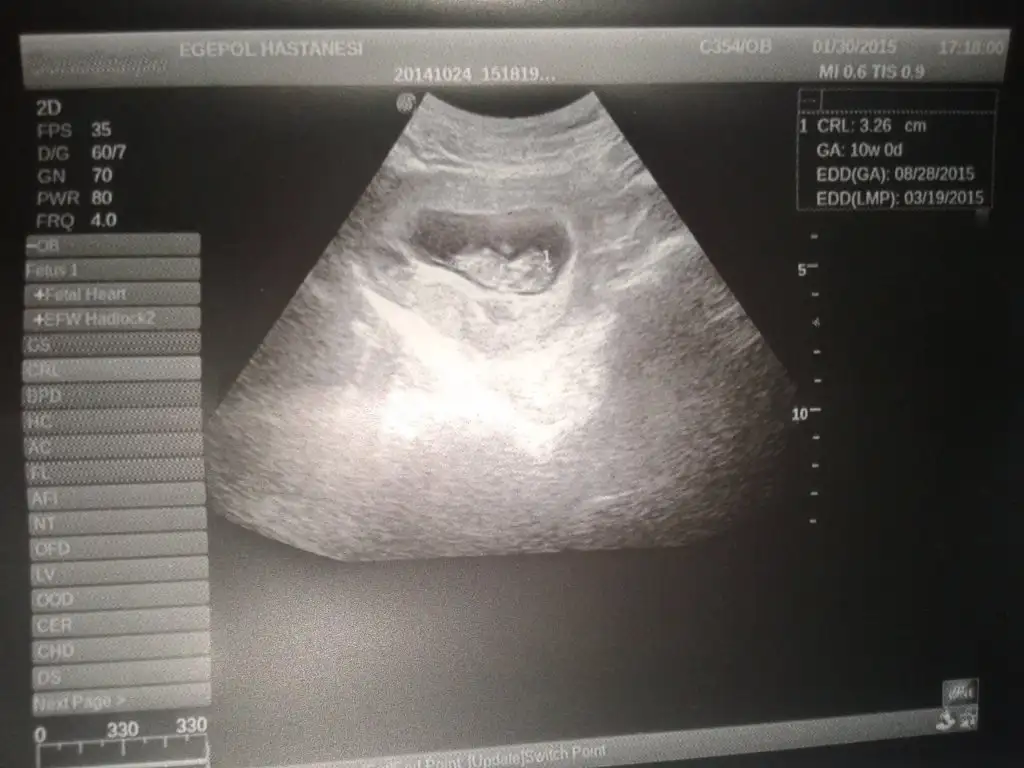

Kızlar budabizim11+2 foto larimmız

• 2015-01-30 14.03.18.webp

16,9 KB · Görüntüleme: 107

• 2015-01-30 14.02.38.webp

15,5 KB · Görüntüleme: 90